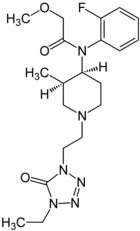

Chemical structures of various fentanyl analogues

Alfentanyl | N-{1-[2-(4-ethyl-5-oxo-4,5-dihydro-1H-1,2,3,4-tetrazol-1-yl)ethyl]-4-(methoxymethyl)piperidin-4-yl}-N-phenylpropanamide | 71195-58-9 |

|

Brifentanyl | N-[(3R,4S)-1-[2-(4-Ethyl-5-oxotetrazol-1-yl)ethyl] -3-methylpiperidin-4-yl]-N-(2-fluorophenyl)-2-methoxyacetamide | 101345-71-5 |

|